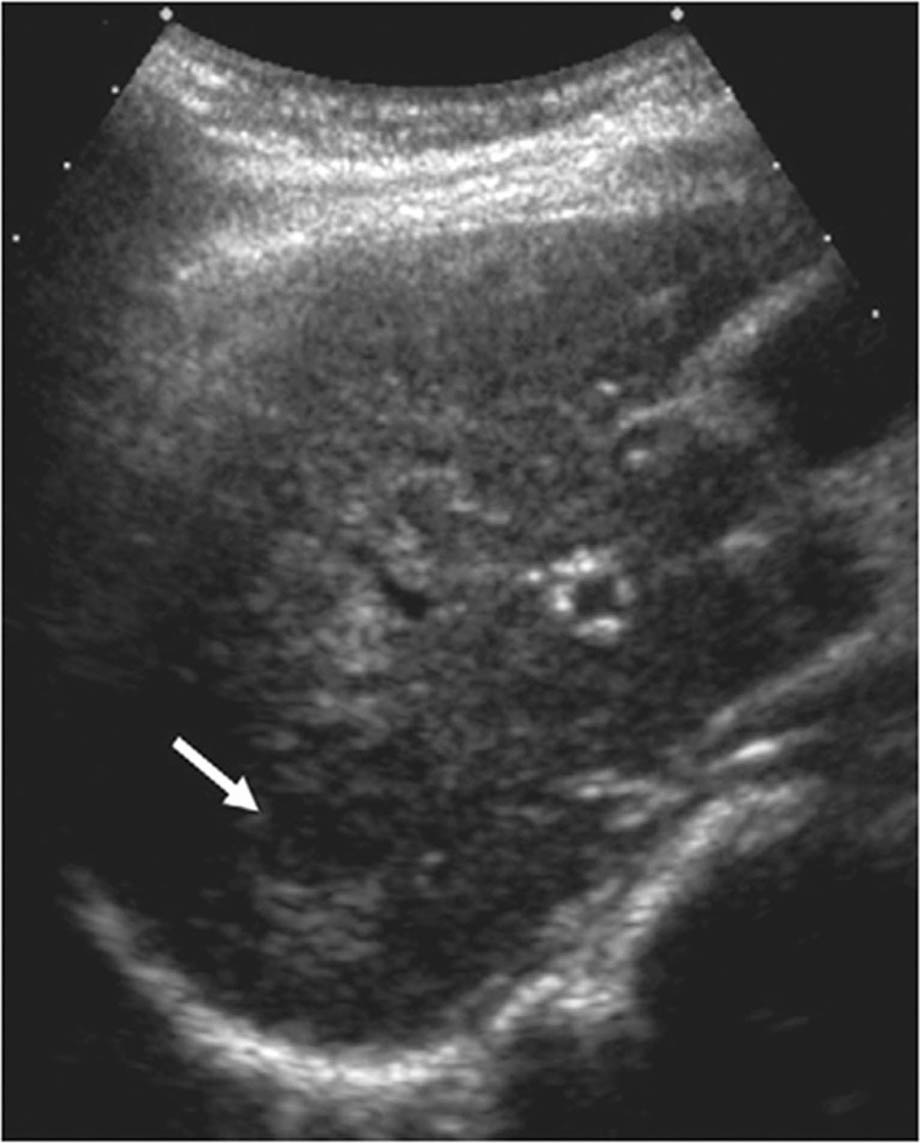

An accurate diagnosis and proper staging assessment are necessary to determine the optimal treatment method for the individual patient with HCC. A liver tumor is usually detected by imaging and its histology confirmed by tissue analysis (55). The various imaging methods include ultrasound (US), which is recommended every six months as a non-invasive low radiation cost-effective screening technique on high-risk patients, and computed tomography (CT) and magnetic resonance imaging (MRI), which are complementary techniques that detect and characterize the different nodules that develop in cirrhosis (Figure 3) (5659). Although there are at least seven staging systems for HCC, the Barcelona Clinic Liver Cancer (BCLC) classification is the most widely and accepted staging system used (Figure 4) (55, 60, 61). The BCLC classification system (Table 1) includes guidelines for the treatment of HCC and has been endorsed by the European Association for the Study of the Liver (EASL), European Organization for Research and Treatment of Cancer (EORTC) and the American Association for the Study of Liver Diseases (AASLD) (60, 62). This system stages an individual as having very early, early, intermediate, advanced, and very advanced (terminal) HCC based on tumor burden, severity of liver disease and his/her performance status matching the recommended evidence-based treatment by the stage of liver tumor (55, 60).

Fig 3

Figure 3. Sensitivity of ultrasound as a surveillance tool for the detection of hepatocellular carcinoma. Ultrasound is recommended every 6 months in high-risk populations for monitoring the development of HCC, as well as in cirrhotic patients. Its sensitivity is around 77% and it can be complemented, if needed, with other imaging modalities, such as computed tomography or magnetic resonance imaging (59).